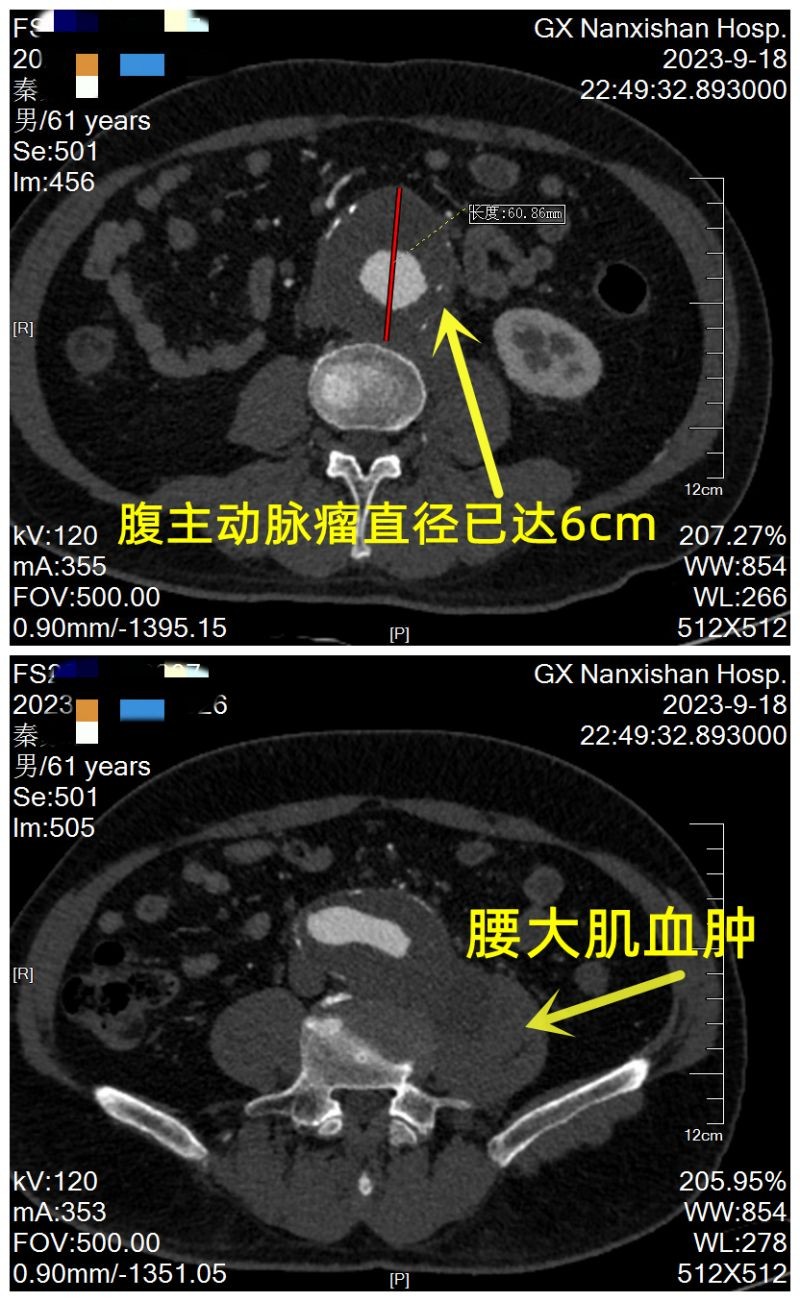

“腹主动脉瘤”号称"人体内不定时炸弹"、“沉默的杀手”。近日,61岁的秦先生因为突发腰痛15小时,转院到了广西壮族自治区南溪山医院。医生为秦先生做主动脉CTA 检查后发现他长了腹主动脉瘤并且已经破裂,如果不及时手术随时可能因为大出血而危及生命。

性命攸关!南溪山医院迅速开启绿色通道,把这项艰巨任务交给了经验丰富的心脏大血管外科。心脏大血管外科团队为秦先生迅速判断病情、制定治疗方案。通过摸查发现,秦先生6年前因为心梗在其他医院放置了2枚冠脉支架,但一直未系统地进行复查,入院后心脏彩超提示他的心脏已明显扩大并心功能低下。秦先生的CTA显示:腹主动脉瘤为短瘤颈,且瘤颈呈锥形,如果使用常规 EVAR 手术,易出现内漏导致手术失败,这给医生出了道难题。

图片2 腹主动脉瘤直径6cm腰大肌血肿